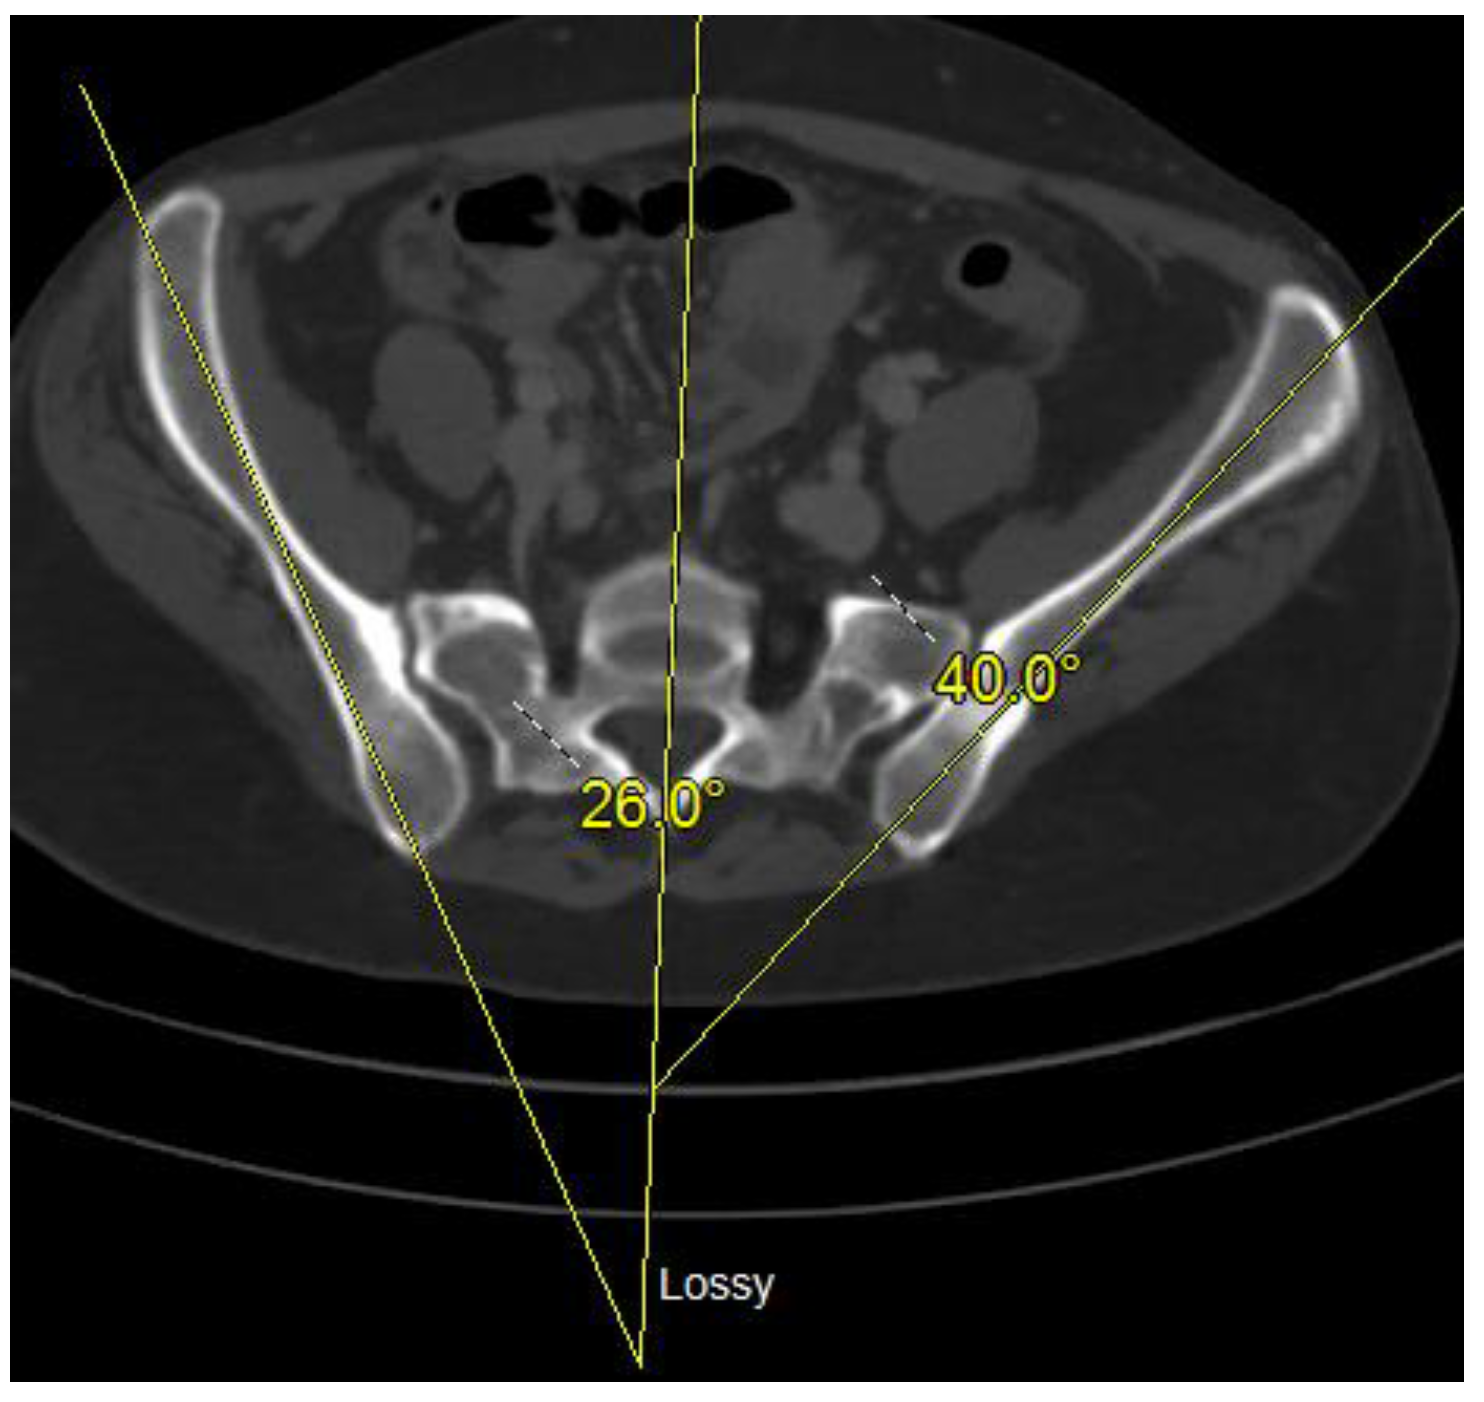

- Kurz, S.; Pieroh, P.; Lenk, M.; Josten, C.; Böhme, J. Three-dimensional reduction and finite element analysis improves the treatment of pelvic malunion reconstructive surgery: A case report. Medicine 2017, 96, e8136. [Google Scholar] [CrossRef]